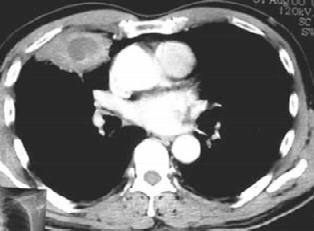

图1-6 男性,53岁,肺脓肿

慢性肺脓肿脓腔壁增厚,内壁不规则,周围有纤维组织增生及邻近胸膜增厚,肺叶收缩,纵隔可向患侧移位,其他健肺发生代偿性肺气肿。血源性肺脓肿在一侧肺或两肺边缘部有多发的、散在的小片状炎症阴影或边缘较整齐的球形病灶,其中可见脓腔及液平面或液化灶。炎症吸收后可呈现局灶性纤维化或小气囊。并发脓胸时,患侧胸部呈大片浓密阴影,若伴发气胸则可见到液平面。侧位X线检查可明确肺脓肿的部位及范围大小,有助于做体位引流和外科手术治疗。

(2)胸部CT检查:可更好了解病变范围、部位及空腔情况。患者多有浓密球形病灶,其中有液化;或有呈类圆形的厚壁脓腔,脓腔内可有液平面出现,脓腔内壁不规则状,周围有模糊炎性影。伴脓胸者尚有患侧胸腔积液改变。